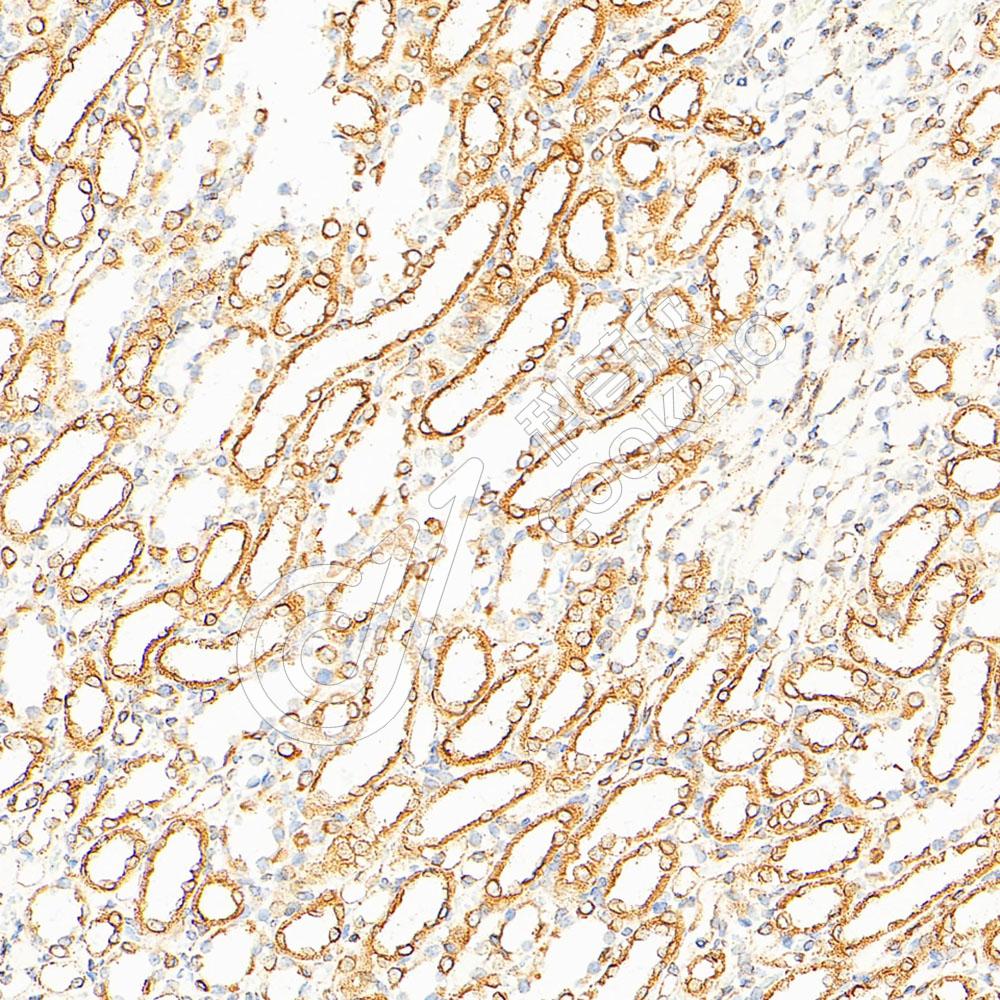

IHC检测Calnexin蛋白(货号 K5454107).

样品: 大鼠肾, 4%多聚甲醛 (货号KSG1101) 固定12-24小时.

抗原修复: Tris-EDTA抗原修复液(pH 9.0) (KSG1203), 100℃, 25分钟.

—抗: 1: 400稀释, 4℃ 孵育过夜.

二抗: S-vision免疫组化多聚二抗(山羊抗小鼠), 即用型(货号KB3903), 室温孵育20分钟.